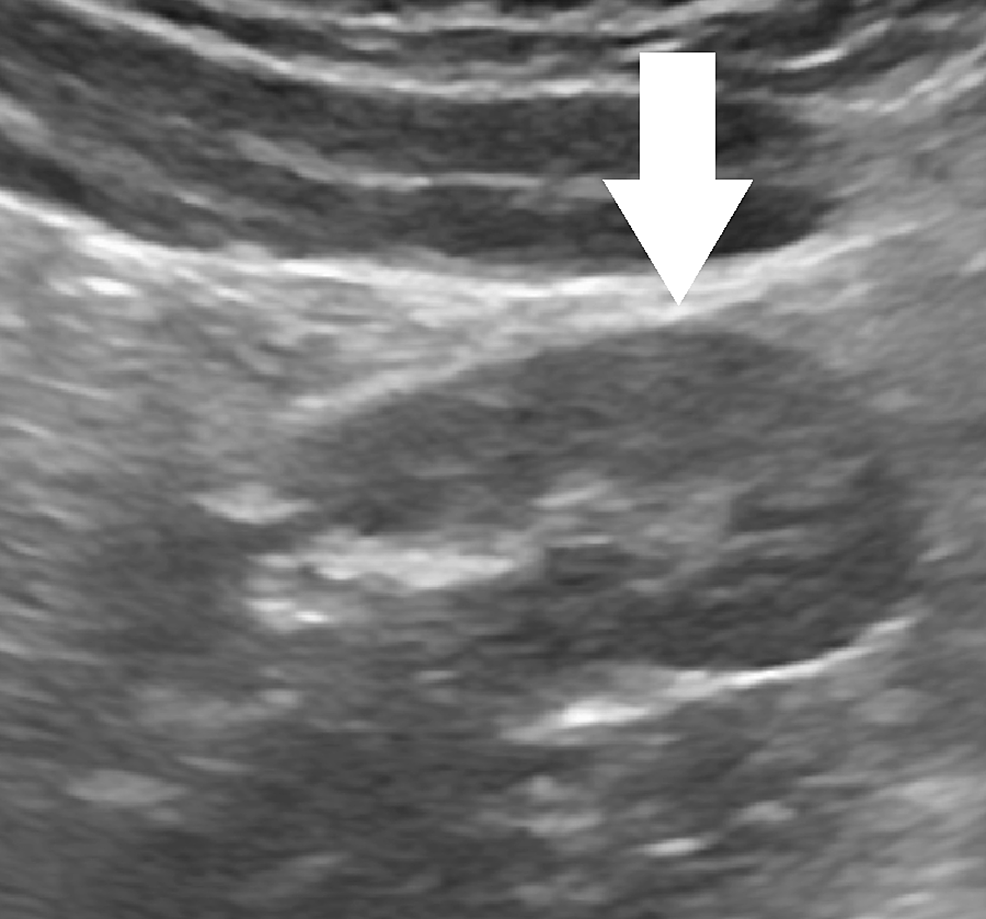

Figure 1 from Evaluation of a Fused Supernumerary Kidney Using MDCT A Fused Supernumerary Kidney Radiology A supernumerary kidney (sk) is an additional kidney with its own capsule and blood supply that is not fused with the ipsilateral. The index case is even more unique in many aspects. First, the accessory kidney is fused to. A supernumerary kidney is an extremely rare congenital anomaly. Supernumerary kidney is a rare congenital anomaly; Congenital renal anomalies comprise of. Fused Supernumerary Kidney Radiology.

Abdominal CT scan axial image shows fusion of right kidney and Fused Supernumerary Kidney Radiology A supernumerary kidney is a rare congenital anomaly of the urinary tract, with fewer than 100 cases documented in the literature, with no difference between the. Crossed fused renal ectopia refers to an anomaly where the kidneys are fused and located on the same side of the midline. Four types of crossed renal ectopia (fig 14) can be seen at. Fused Supernumerary Kidney Radiology.